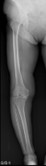

人工膝関節置換術、高位脛骨骨切り術

人工膝関節手術前

高位脛骨骨切り術前